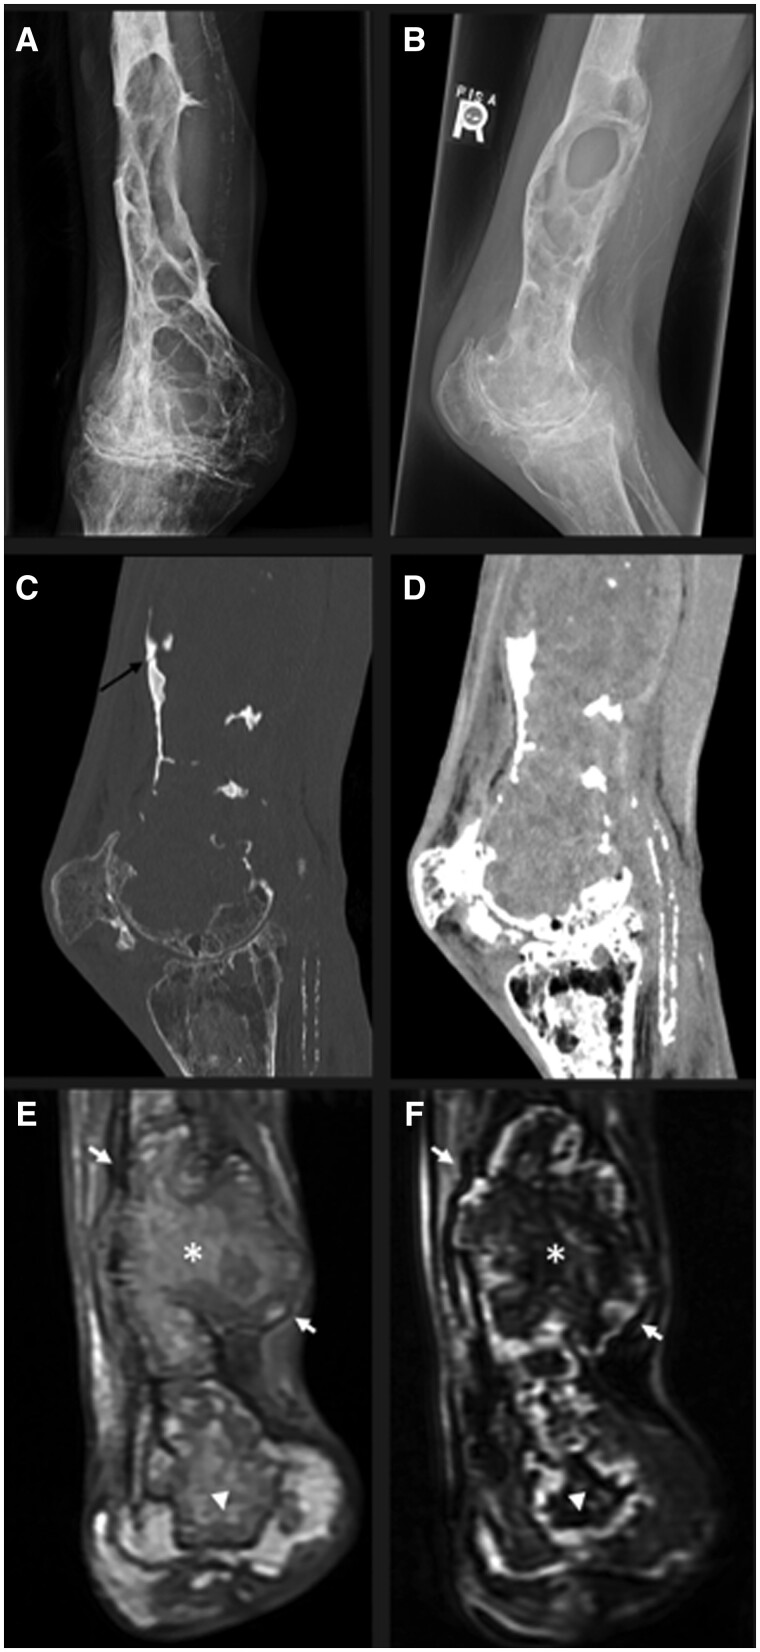

Pseudotumours are uncommon complications of haemophilia, occurring in 1%-2% of patients with haemophilia.1 , 2 It is a slowly expanding haematoma as a result of recurrent haemorrhage, surrounded by a fibrous capsule. It can occur in both bone and soft tissue, and progressive enlargement may result in bone destruction and/or muscle and skin necrosis. Pseudotumours by themselves are usually painless though its mass effect can result in nerve compression resulting in pain or neurologic symptoms. It may also predispose to pathologic fractures (as in our case) and superimposed infections.2 , 3.